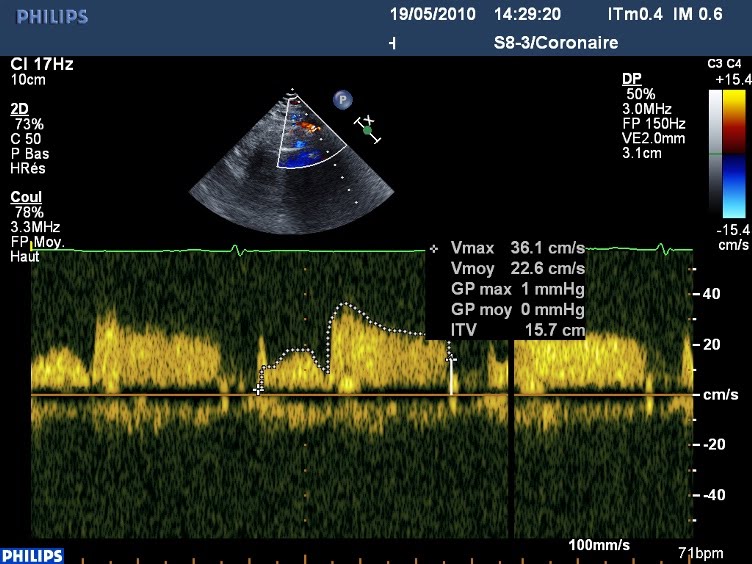

L’examen, par ailleurs négatif, est complété par une mesure de réserve coronaire, l’ITV du flux dans l’IVA distale est multiplié par deux sous Dobutamine, ce qui est une réponse normale.

Au repos :